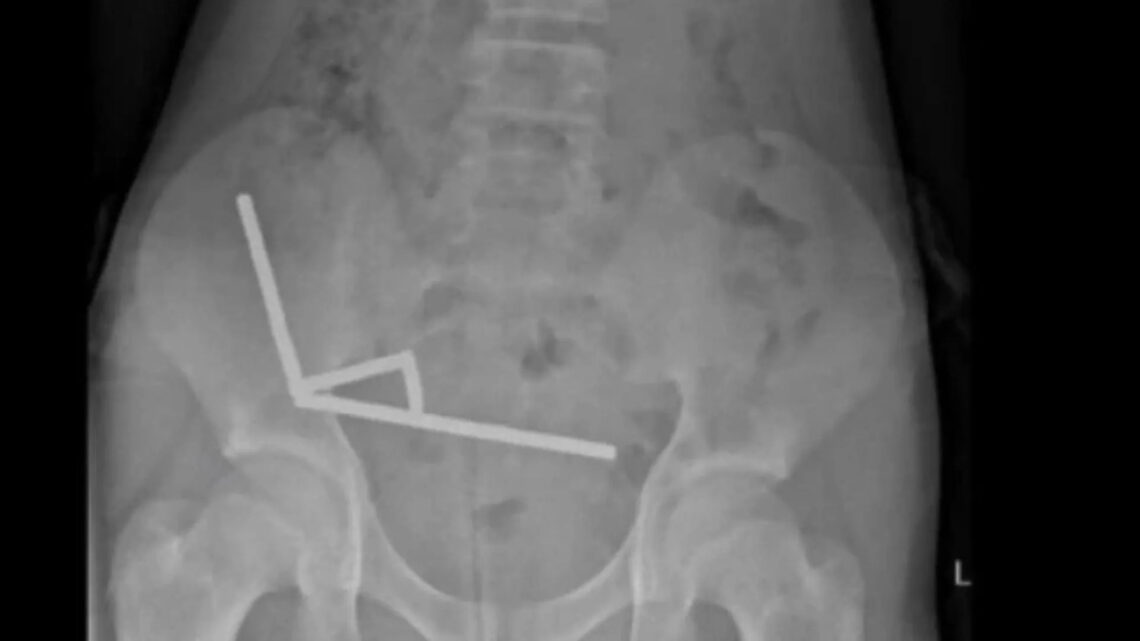

O adolescente foi internado, após quatro dias de dores abdominais, e teve de passar por uma cirurgia de emergência. Os exames feitos antes da cirurgia mostravam correntes de ímãs em partes do intestino, ligadas pela força magnética. Tal ligação resultou em um necrose por conta da pressão, e quase houve uma perfuração intestinal. Na operação foram encontradas quatro áreas necrosadas, e parte do intestino do menino teve de ser retirado.